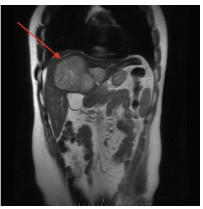

Multidisciplinary treatment of hepatocellular carcinoma with tumor thrombosis in the left portal vein: A case report

Jihong YANG, Guoxiang CHEN, Mo ZHOU, Jisen ZHAO, Yuan WANG, Yuanlong ZHOU

2021, 37(3): 666-679. DOI: 10.3969/j.issn.1001-5256.2021.03.031

Abstract(1185) HTML (567) PDF (3239KB)(69)

Abstract: